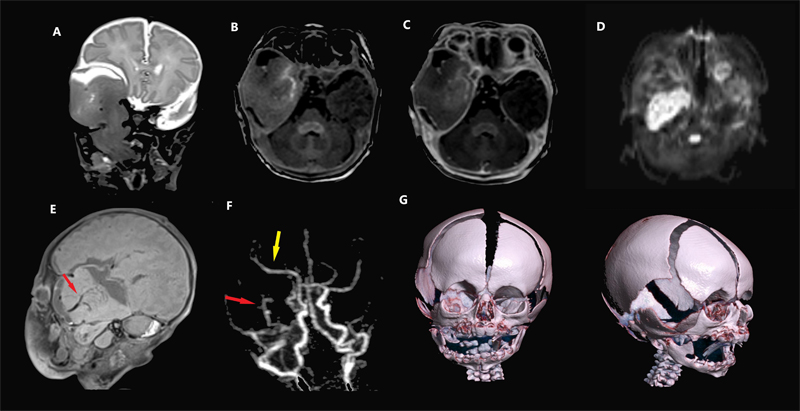

Magnetic resonance imaging (MRI) of the skull base revealed a large cystic and solid extra-axial mass in the right middle cranial fossa, displacing the right temporal lobe and extending into the right infratemporal fossa through a large skull base defect, as well as cleft palate. Furthermore, the mass protruded into the oropharynx (Figure 1A). The adjacent brain parenchyma appeared radiologically separate from the mass. The mass had signal intensity resembling brain parenchyma except for faint enhancement at the center and diffusion restriction in the infratemporal component (Figure 1B–D). The vascular supply of this mass appeared separate from the adjacent brain with its own feeding vessel and distal perfusion (Figure 1E–F). MRI sequences demonstrating diffusion restriction suggested this lesion could represent a malignancy. However, the lesion did not invade adjacent structures and appeared to induce bony erosion not by infiltration but by resorption and remodeling (Figure 1G). Therefore, a benign diagnosis was favored.

Figure 1. Head and neck imaging. Coronal T2 MRI (A) shows a mass extending from the middle cranial fossa through a skull base defect into the right infratemporal fossa. The adjacent normal brain parenchyma is displaced but not involved by the mass, with a clear cerebrospinal fluid (CSF) cleft separating the two. Axial pre-contrast (B) and post-contrast (C) T1 MPRAGE images show minimal enhancement at the center, but the majority of the mass is non-enhancing. Axial diffusion-weighted imaging (D) shows diffusion restriction in the infratemporal mass, suggestive of hypercellularity, a feature often concerning for an aggressive tumor, though this can also be seen in benign lesions. Sagittal T1 SPACE MRI (E) and post-contrast MRA (F) show a prominent vascular pedicle (red arrows) in the center of the mass and the displaced right middle cerebral artery (yellow arrow). 3D renderings of the skull (G) show budging of the squamosal temporal bone and widening of the suture rather than osseous destruction.